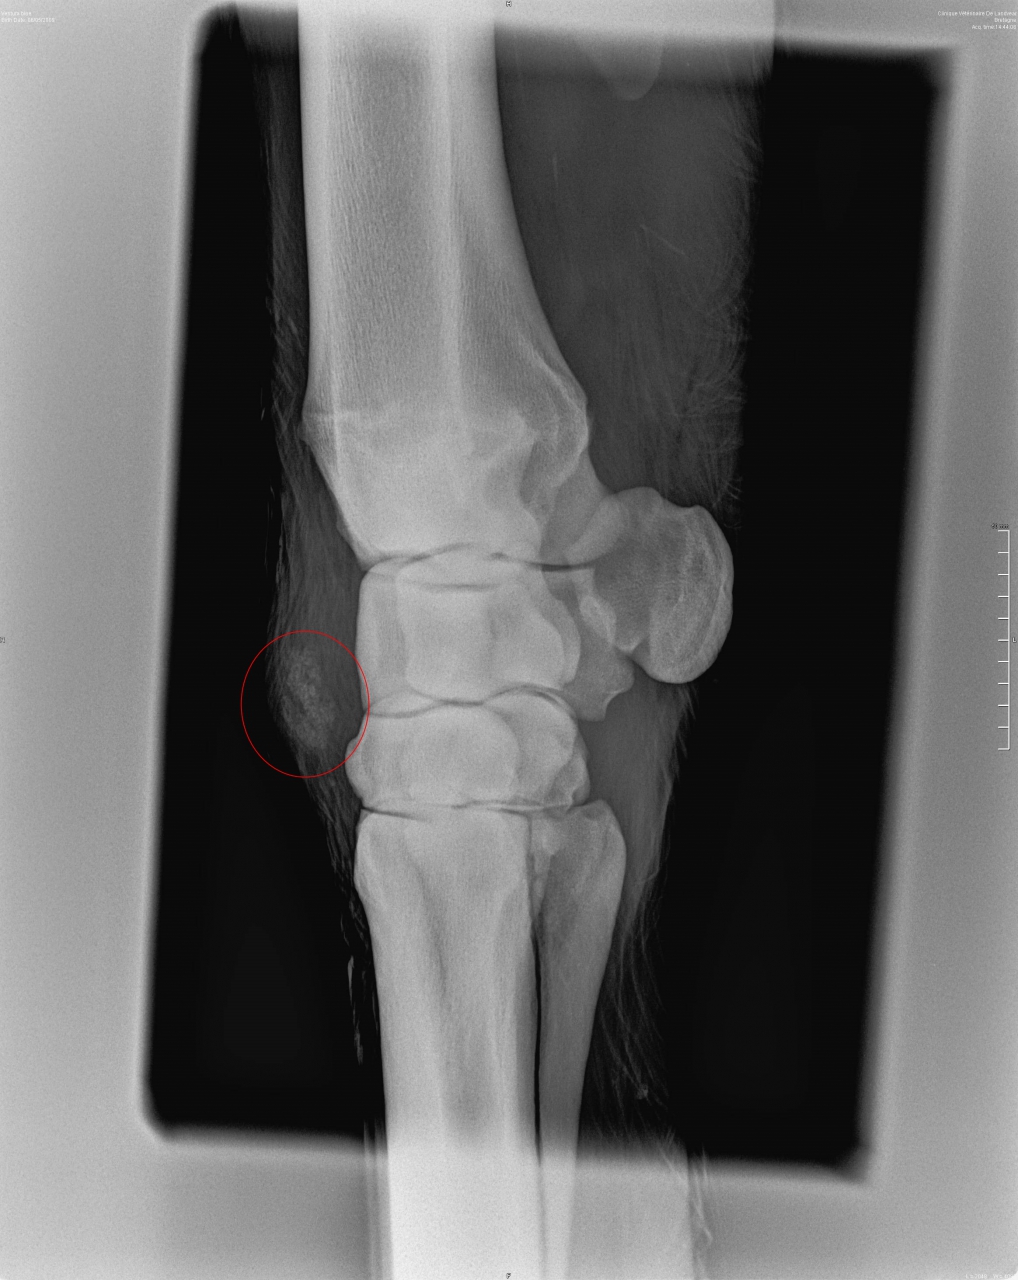

| Dire merci | Bonsoir, Pour poser un peu le problème, ma jument a depuis un bon mois un soucis au genou, surement dû à un coup. Au début c'était engorgé puis ça a vite dégonflé avec application d'argile. Petite boiterie mais rien de bien méchant. Le veto l'avait vu et conseillé d'appliquer de l'ekyflogil. Par la suite j'ai fais des emplâtres d'argile, plutôt efficace. Toujours un mini mini boiterie. On a été à la mer marcher dans l'eau etc... Sur le genou il y a une bosse dure, non mobile, non douloureuse (je peux tripoter la bosse, lui plier le membre sans soucis). Bref, voyant que la masse est toujours là je décide de faire des radios/echo redoutant le suros. Je l'envoie en clinique, le veto touche et me dit d’emblée que c'est surement un suros... il fait les clichés, un de face et un de profil. Je vais avec lui voir les résultats, bon non finalement ce n'est pas un suros. On fait ensuite une echo où on ne voit pas grand chose. Pas simple de dire ce que c'est exactement, le veto évoque un nodule fibreux indépendant du tendon extenseur. Alors le protocole qu'il m'indique de suivre est, ekyflogyl pendant encore une semaine 2x par jour. Si le nodule évolue et/ou est toujours gênant il faudra pratiquer une ablation. Je sais qu'il y a des vetos sur le forum, au vu des radios j'aimerais avoir des avis, sur cette chose j'attend pas de miracles, juste si quelqu'un peut m'en dire plus... vaut mieux opérer direct ? merci d'avance. celle de profil avec la masse entourée en rouge ![]() et celle de face, ou on ne voit pas grand chose ![]() |